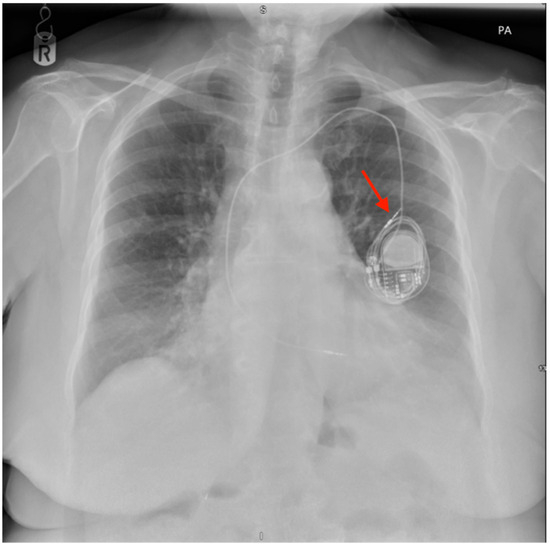

Twiddler’s Syndrome: Predictors, Prevention, and Outcomes in a Case Series

Background/Objectives: Twiddler’s syndrome is an uncommon but clinically important complication of implantable cardiac devices, in which generator rotation within the pocket results in lead torsion, lead retraction, and device malfunction. Recurrence can necessitate repeated surgical intervention and may be preventable through early risk identification and procedural strategies. Methods: We describe a single-centre case series of three female patients with pacemaker-associated Twiddler’s syndrome. Clinical presentation, timing of lead retraction, management strategies (including pocket location and fixation approach), recurrence, and follow-up outcomes were reviewed. Results: All patients were older women and developed symptomatic device failure early after implantation, with radiographic confirmation of lead retraction and coiling occurring within three weeks in all cases. Recurrence was observed when enhanced preventive measures were not employed. Notably, in one patient, recurrence occurred after an initial revision in a second prepectoral pocket, prompting subsequent reimplantation in a subpectoral location with reinforced fixation and structured patient and family counselling, after which no further recurrence occurred at one year. In the remaining cases, revision with reinforced generator fixation and counselling was associated with stable lead position and satisfactory device function during follow-up. Conclusions: Twiddler’s syndrome most commonly presents in the first weeks following implantation. Proactive identification of at-risk patients and consideration of reinforced fixation and pocket strategies at the index procedure may reduce recurrence and avoid repeat interventions.

Figure 1